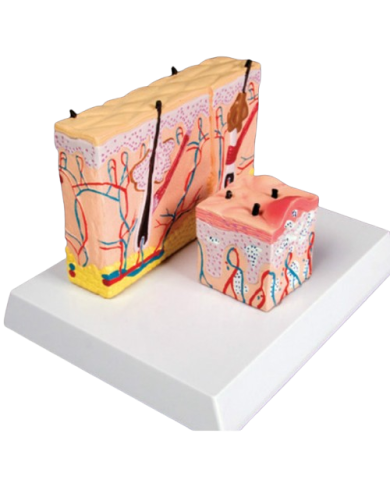

Modello anatomico PER FORNITURE CASE FARMACEUTICHE

Modello anatomico PER FORNITURE CASE FARMACEUTICHE

Modello anatomico PER FORNITURE CASE FARMACEUTICHE

Modello anatomico PER FORNITURE CASE FARMACEUTICHE

Modello anatomico PER FORNITURE CASE FARMACEUTICHE

Modello anatomico PER FORNITURE CASE FARMACEUTICHE

Modello anatomico PER FORNITURE CASE FARMACEUTICHE

Modello anatomico PER FORNITURE CASE FARMACEUTICHE

Modello anatomico PER FORNITURE CASE FARMACEUTICHE

Modello anatomico PER FORNITURE CASE FARMACEUTICHE

Modello anatomico PER FORNITURE CASE FARMACEUTICHE

Modello anatomico PER FORNITURE CASE FARMACEUTICHE

Modello anatomico PER FORNITURE CASE FARMACEUTICHE

Modello anatomico PER FORNITURE CASE FARMACEUTICHE

Modello anatomico PER FORNITURE CASE FARMACEUTICHE

Modello anatomico PER FORNITURE CASE FARMACEUTICHE

Modello anatomico PER FORNITURE CASE FARMACEUTICHE

Modello anatomico PER FORNITURE CASE FARMACEUTICHE

Modello anatomico PER FORNITURE CASE FARMACEUTICHE

Modello anatomico PER FORNITURE CASE FARMACEUTICHE

Modello anatomico PER FORNITURE CASE FARMACEUTICHE

Modello anatomico PER FORNITURE CASE FARMACEUTICHE